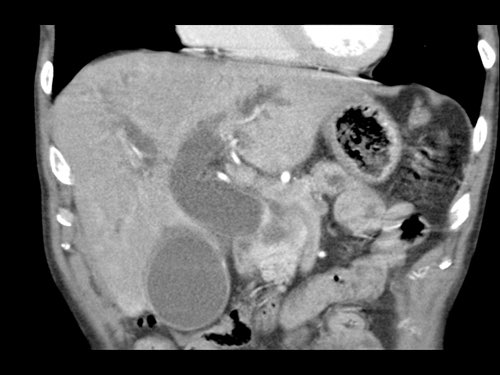

Ở những bệnh nhân dự kiến phẫu thuật tụy, điều quan trọng là cần đặc biệt chú ý tìm kiếm nguyên ủy bất thường của động mạch gan phải hoặc động mạch gan chung.

Các động mạch này xuất phát từ phía phải của động mạch mạc treo tràng trên (SMA) và đi qua vùng lân cận đầu tụy, làm tăng nguy cơ xâm lấn của khối u hoặc tổn thương do phẫu thuật.

Tần suất được ghi nhận của các bất thường đặc hiệu này lần lượt là 11-21% và 0,5-5%.

Sự liên quan mạch máu được đánh giá rõ hơn trên ảnh tái tạo mặt phẳng đứng dọc. Có sự áp sát 90 – 180° của động mạch gan phải thay thế (mũi tên trắng) bởi ung thư biểu mô tuyến đầu tụy (đầu mũi tên trắng).

Động mạch gan trái nguyên bản đi theo hướng ra trước hơn, tĩnh mạch cửa nằm ở giữa.

Cuộc phẫu thuật là cắt bỏ diện R1.